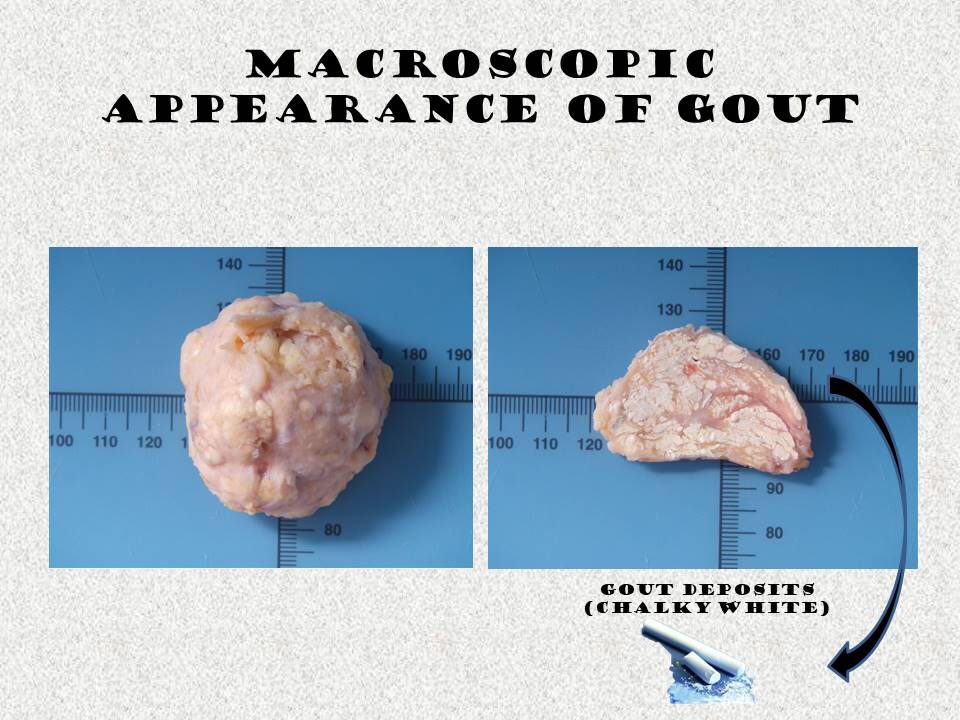

Gross description

- Specimens of patients with history of gout / gross suspicion for crystals should not be processed in formalin

- Uric acid crystals are water soluble and destroyed in routine formalin processing

- They require alcohol fixation and anhydrous processing for microscopic visualization (The University of Chicago: Gross Pathology Manual [Accessed 12 August 2022])

- If specimen is processed in formalin, chalky material should be removed from sample and scraped on slide for examination

- Small white flecks to large deposits of crystals that may appear white or tan and chalky or crumbly

- This appearance is associated with sugar icing, snow-like, powdery or toothpaste-like material

Gross images